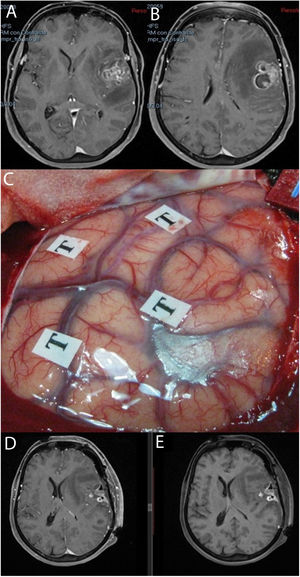

Imágenes de resonancia magnética en la secuencia T1 con contraste (A, B) que muestran una tumoración correspondiente a glioblastoma situada en la región opercular izquierda. Se empleó cirugía con mapeo cerebral intraoperatorio en paciente despierto (C). Las resonancias magnéticas postoperatorias con (D) y sin contraste intravenoso (E) muestran cambios posquirúrgicos, con restos hemáticos en ausencia de tumoración residual, todo ello sin que tuviera lugar un empeoramiento en el lenguaje.

Se recogieron los datos pertenecientes a la edad, sexo, fecha de diagnóstico, Karnofsky Performance Status (KPS), enfoque terapéutico con o sin cirugía y modalidad de esta, intervalo libre de progresión desde la cirugía inicial, número de intervenciones, modalidad de tratamiento adyuvante y causa del fallecimiento. Del mismo modo, se obtuvieron de las imágenes e informes radiológicos los datos relacionados con la presencia de tumor en región elocuente, considerando como tal la extensión del tumor a la región tálamo-capsular, corona radiata o centro semioval, lóbulo central, áreas relacionadas con el lenguaje (opérculo frontal del hemisferio dominante, circunvolución supramarginal, lóbulo temporal dominante y transición entre dichas zonas). Para la extirpación de los tumores en dichas localizaciones se contó con la ayuda de monitorización neurofisiológica intraoperatoria (fig. 1) o cirugía con paciente despierto (fig. 2) con el fin de maximizar el grado de extirpación y limitar el riesgo de déficit neurológico postoperatorio (fig. 3).